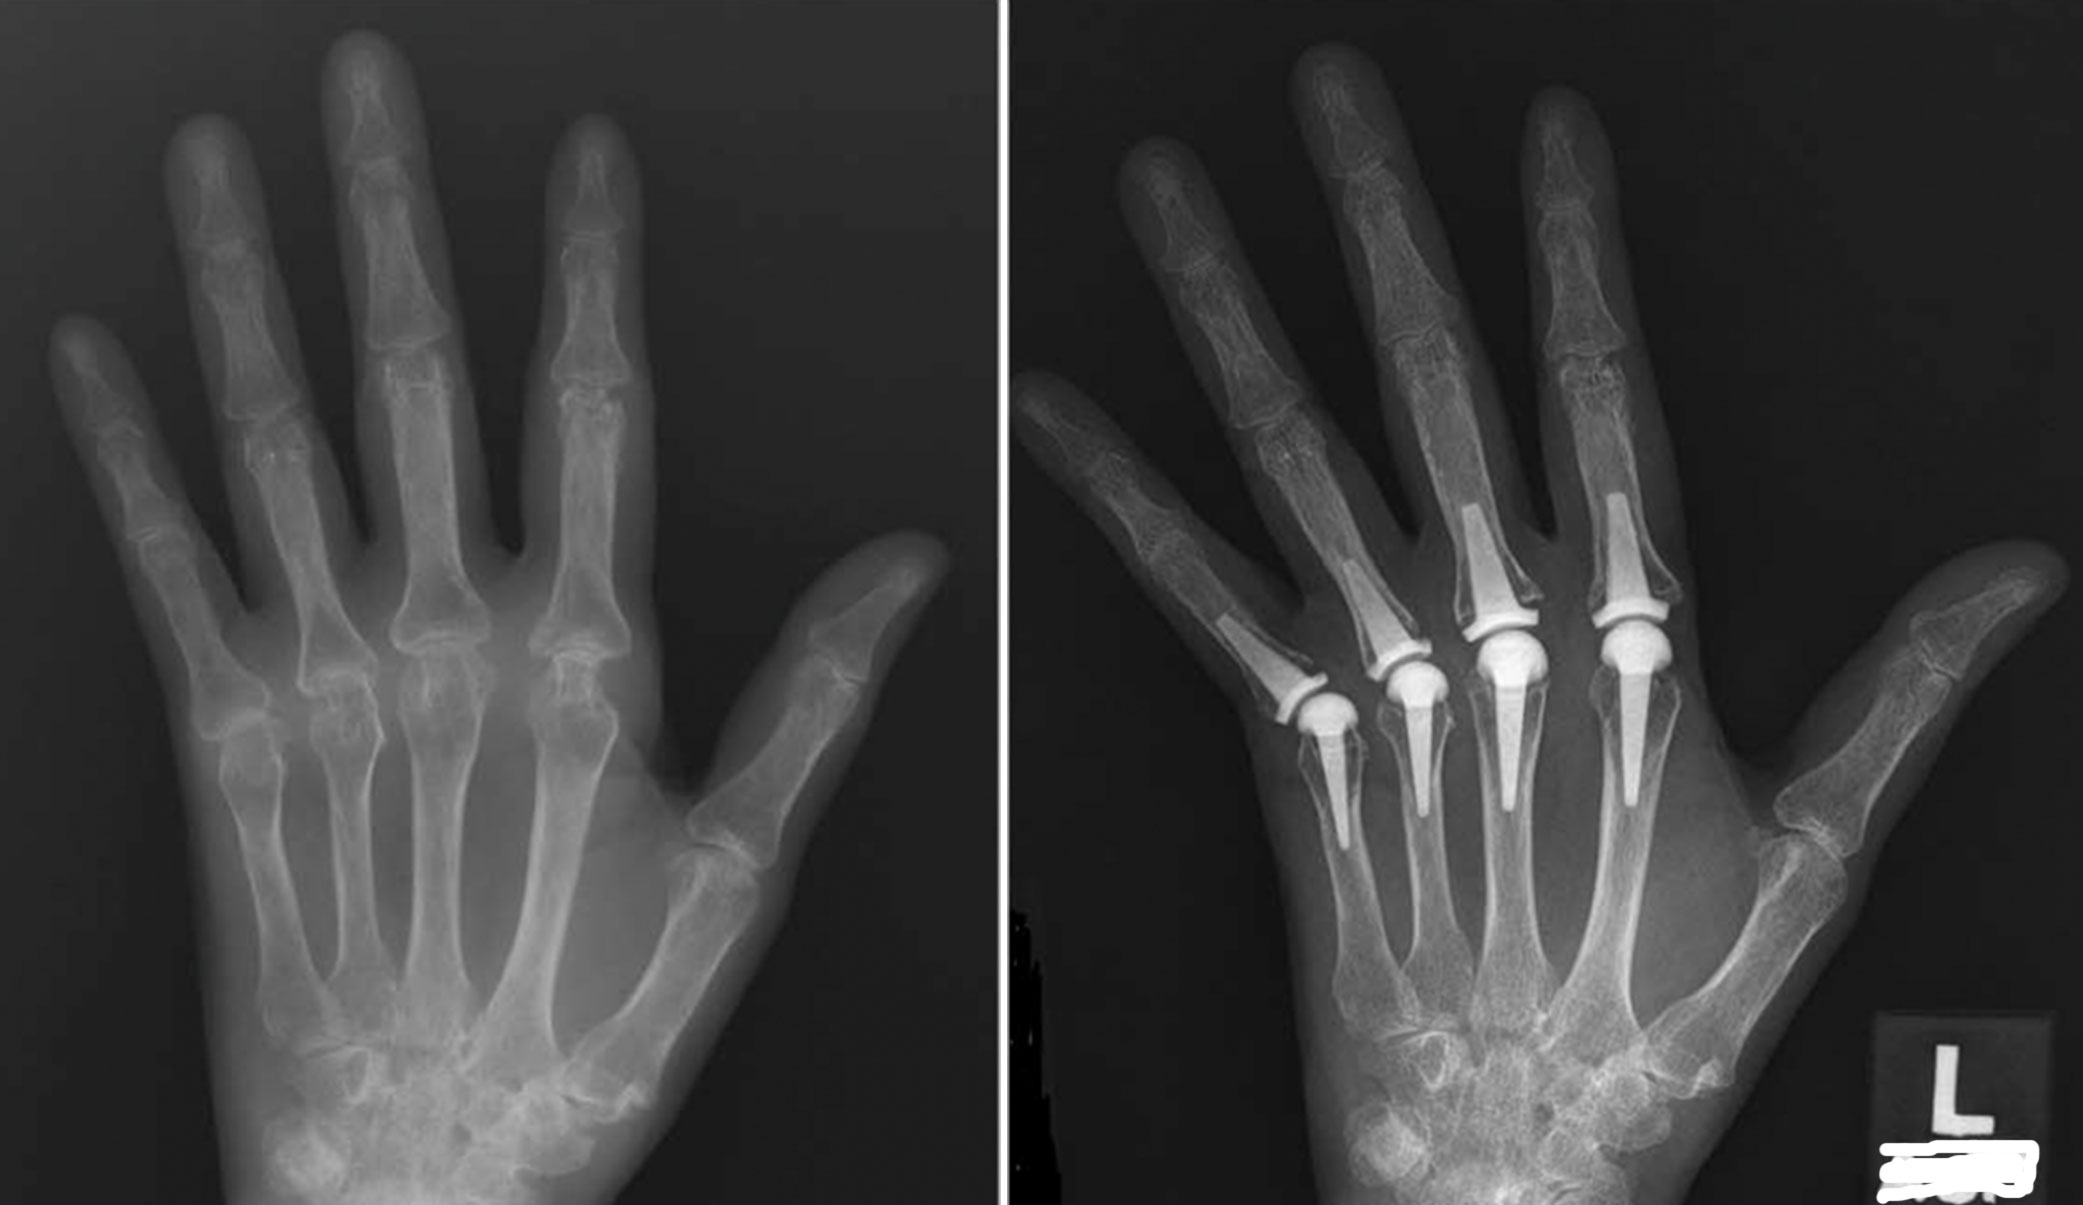

X-ray Showing Finger Arthritis and Finger Joint Replacement

(Left) X-ray of a patient with arthritis throughout the hand, particularly affecting the MCP joints. (Right) X-ray of the patient after replacement of the index through little finger MCP joints with pyrocarbon implants.

Reproduced from Carlson Strother C, Moran S, Rizzo M. Small Joint Arthroplasty of the Hand: An Update on Indications, Outcomes, and Complications. J Am Acad Orthop Surg 2023;31:793-801.